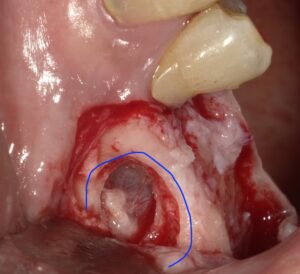

○で囲った部分、骨に穴を開けます。この時

粘膜を巻き込んで破らないように細心の注意を払います。

点線の中が粘膜です。シュナイダー膜ともいわれます。

生卵の内側にある膜ほどの厚みしかありません。